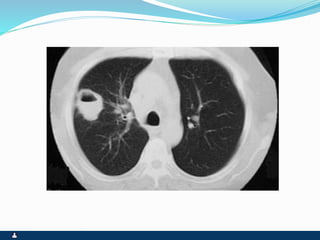

BRONQUIECTASIA

 DILATAÇÃO BRÔNQUICA IRREVERSÍVEL POR

DESTRUIÇÃO DAS ESTRUTURAS ANATÔMICAS

QUE FORMAM A PAREDE

 PÓS-INFECÇÃO (PNEUMONIA)

 PÓS-OBSTRUÇÃO ( CORPO ESTRANHO, ROLHAS

DE SECREÇÃO, TUMORES BRÔNQUICOS,

CONGÊNITA)

SINTOMAS SINAIS

 FACIES DE DOENÇA CRÔNICA

 INFECÇÃO DE REPETIÇÃO

 FEBRE OU FEBRÍCULA SEM

CAUSA APARENTE

 TOSSE PRODUTIVA CRÔNICA

 BRONCORRÉIA E DRENAGEM

POSTURAL

 HEMOPTÓICOS OU

HEMOPTISE

 VÔMICA EVENTUAL

 ESTADO GERAL NORMAL OU

EMAGRECIMENTO

 CIANOSE COM

HIPOCRATISMO DIGITAL

 EXPANSIBILIDADE REDUZIDA

 FTV REDUZIDO, NORMAL OU

AUMENTADO

 MV REDUZIDO

 RONCOS E SIBILOS

 ESTERTORES BRÔNQUICOS E

ALVEOLARES